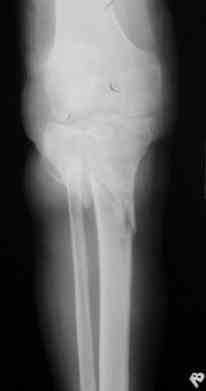

Опять мало информации. Это снимки от августа 2006. А что сейчас в двух проекциях? Что растет в посевах? Насколько заинтересован коленный сустав: движения, синовит? Чего хочет больной?

Р-граммы за март и апрель

Р-граммы и фото за 4.05.2007 - 7-е сутки после операции.

Ход операции - линейным разрезом по передней поверхности голени обнажена зона ложного сустава большеберцовой кости. От кости отсепарованы медиально м/ткани. Из зоны ложного сустава убраны рубцовые ткани, мобилизован дистальный отломок. По передней поверхности удалены два осколка, связанных грануляциями. Произведено удаление грануляционной ткани из проксимального отломка (на вид сине-серого цвета), "чистого" гноя не было. Затем произведено наложение аппарата и репозиция отломков. По передне-медиальной поверхности образовался дефект до 4х2х2 см + полость в проксимальном отломке. Удаленные осколки очищены от грануляций, уложены в место дефекта, зажаты между отломками. После иссечения раны по передней поверхности, находящейся рядом с операционной раной, последняя ушита с большим натяжением.

Перелом мыщелка сросся. Проксимальный отломок очень порозный.